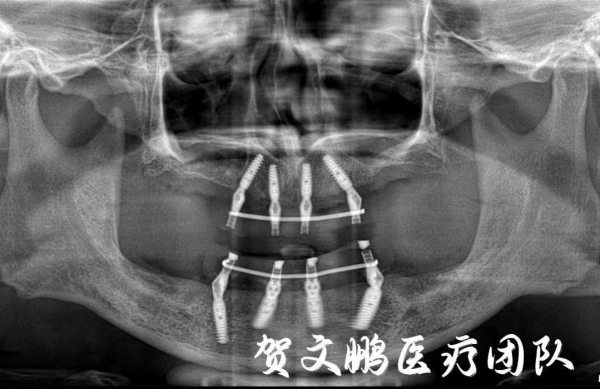

對於楊教授這種情況,賀文鵬醫療團隊為他設計了一個數字化全口種植的方案:利用計算機數字化設計,在上下頜分別植入4顆種植體作為“橋墩”,將個性化製作的單頜全口義齒與同一端的4根“橋墩”連線固定,從而形成完整的“橋體”結構。

服下這麼一劑定心丸,楊教授也下定決心好好治治這一口壞牙了!手術當天,在全麻下,麻醉師負責檢測血壓變化,輔以藥物調控,而賀文鵬醫生團隊則使用專業的種植器械,在數字化導板的輔助下,將種植體分別植入上下頜骨,順利完成了微創精確的種植手術。